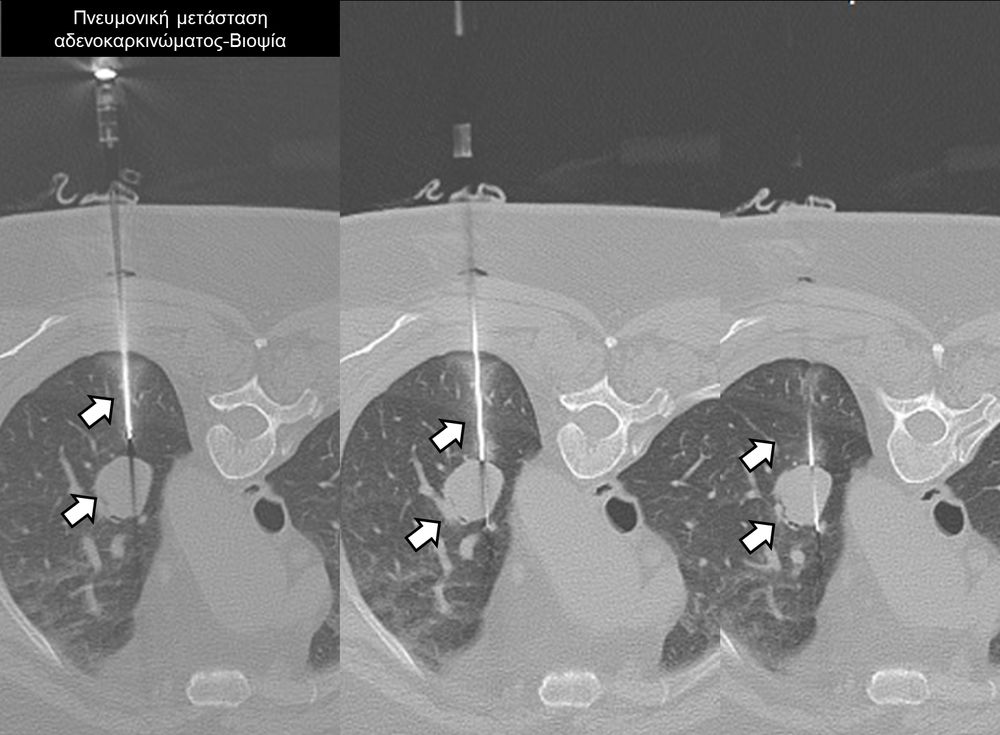

Η διαδερμική βιοψία είναι μία ελάχιστα επεμβατική μέθοδος λήψης υλικού από τον όγκο για κυτταρολογική και ιστολογική εξέταση, από εστιακές αλλοιώσεις του ήπατος, πνεύμονα, νεφρού κλπ. Συστήνεται από τον κλινικό ιατρό ανάλογα με το είδος και το μέγεθος της βλάβης και πραγματοποιείται με ασφάλεια από επεμβατικό ακτινολόγο με την καθοδήγηση αξονικού τομογράφου ή υπερήχων. Στη σύγχρονη ογκολογική θεραπεία όπου γίνεται προσπάθεια καταπολέμησης του καρκίνου σε μοριακό επίπεδο κρίνεται αναγκαία η ακριβής ιστολογική ταυτοποίηση του όγκου ώστε να εφαρμοσθεί εξατομικευμένη θεραπεία για το βέλτιστο αποτέλεσμα. Οι κατευθυνόμενες βιοψίες στοχευουν στο να παρέχουν στον κλινικό ογκολόγο το απαραίτο ιστοπαθολογικό υλικό που θα του επιτρέψει να εφαρμόσει την κατάλληλη θεραπεία για τον ογκολογικό ασθενή.